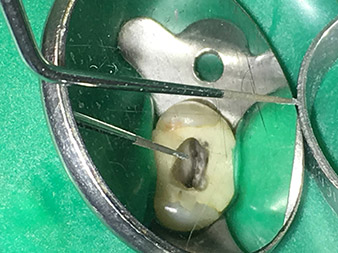

Dr. Nouraie: Yes, in my opinion. The tips allow you to work in a particularly atraumatic and minimally invasive manner. Among other steps, this applies to the exposure of the individual canal accesses, preparation of the cavity in the area of the pulp chamber, rounding off of the canal openings at the transition from the bottom of the chamber to the root canal and preparation of the coronal regions of the root canals.

It is also possible to activate the rinsing fluid in the root canal system. What’s more, it makes a range of special indications such as the revision of broken-off instruments and root posts possible.

Dr. Nouraie: I particularly enjoy working with the 1E tip. It is perfectly suited to activating the rinsing fluid in the root canal system. The delicate design of the tip allows you to reach deep sections of the canal too and ensure optimal activation.

Thanks to the material reinforcement at the transition from the working end to the shaft, the risk of this thin instrument breaking has now been minimized.

Pictures: Dr. Shahrad Nouraie Ashtiani, Bremen